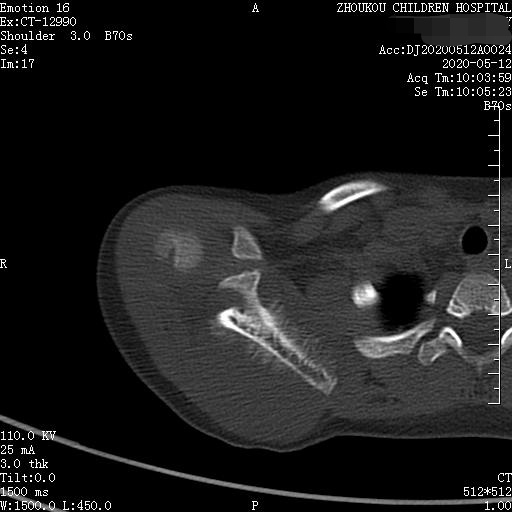

通过CT平扫发现:右侧肩胛骨骨质密度不均,骨质内可见“虫食样”低密度影,骨质边缘可见多发放射状骨针,呈“日光射线征”。周围软组织明显肿胀,肌间隙模糊。CT检查意见:考虑:右肩胛骨占位,骨肉瘤可能,不除外其它恶性肿瘤病变,请结合临床及相关检查注意复查。 影像鉴别诊断:骨肉瘤是指起源于骨间叶组织,遗留形成骨细胞直接形成骨样组织为特征的恶性肿瘤,是比较常见的骨恶性肿瘤,好发于十到二十岁青少年,骨肉瘤常见于管状骨,股骨远端胫骨近端最多见,表现为疼痛局部肿胀运动障碍,实验室检查都有碱性磷酸酶升高。

二、根据骨质破坏和肿瘤骨的多少,骨肉瘤可以分为三型,液化型以肿瘤新生骨为主,溶骨型是以骨质破坏为主,混合型新生骨的形成和骨质破坏并存,x线表现是不规则的骨质破坏伴浸润,可见日光样和放射状骨膜反应,骨膜新生骨在破坏可形成考特曼三角,骨内可见云状、絮状、针状、放射状肿瘤骨伴软组织肿块而形成。